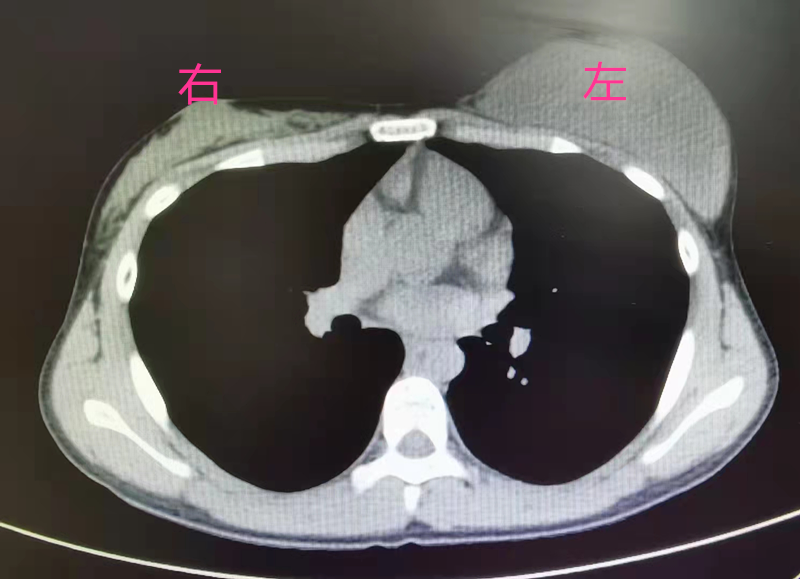

患者小雪(化名)家住汉川,一年半前,她自觉左侧胸部逐渐增大,正处于青春期的她以为是正常的生长发育就一直没有放到心上。春节期间,小雪外出打工的父母回汉川过年,妈妈聂女士在洗澡时发现女儿左右胸部大小差别巨大,感觉不对劲的聂女士赶紧带着小雪去了医院,在当地医院经乳腺彩超提示,左侧乳腺实质病灶有两个,大的约有9.2×3.0×8.6㎝,小的约有0.7×0.3㎝,怀疑恶性肿瘤可能。

为了进一步确诊和治疗,聂女士带着小雪来到了湖北省第三人民医院(湖北省中山医院)甲乳外科。接诊医生发现,小雪左侧胸部如成人大小,犹如乳房假体在内,右侧胸部还尚未发育,进一步完善相关检查后,建议小雪手术治疗。